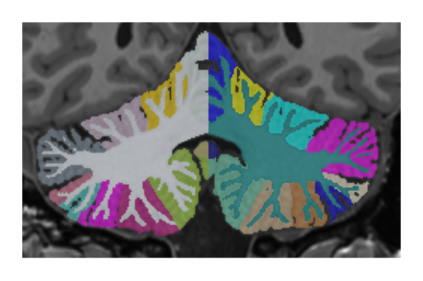

This paper introduces a novel multimodal and high-resolution human brain cerebellum lobule segmentation method. Unlike current tools that operate at standard resolution ($1 \text{ mm}^{3}$) or using mono-modal data, the proposed method improves cerebellum lobule segmentation through the use of a multimodal and ultra-high resolution ($0.125 \text{ mm}^{3}$) training dataset. To develop the method, first, a database of semi-automatically labelled cerebellum lobules was created to train the proposed method with ultra-high resolution T1 and T2 MR images. Then, an ensemble of deep networks has been designed and developed, allowing the proposed method to excel in the complex cerebellum lobule segmentation task, improving precision while being memory efficient. Notably, our approach deviates from the traditional U-Net model by exploring alternative architectures. We have also integrated deep learning with classical machine learning methods incorporating a priori knowledge from multi-atlas segmentation, which improved precision and robustness. Finally, a new online pipeline, named DeepCERES, has been developed to make available the proposed method to the scientific community requiring as input only a single T1 MR image at standard resolution.